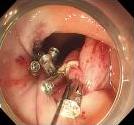

• 可旋转重复开闭软组织夹联合外科尼龙缝合线法闭合结直肠内镜黏膜下剥离术后缺损的临床应用价值

2025, 31(12):77-82. DOI: 10.12235/E20250091

摘要 (77) HTML (65) PDF 1.86 M (64) 评论 (0) 收藏

摘要:目的 探讨可旋转重复开闭软组织夹联合外科尼龙缝合线法(ROLM)闭合结直肠内镜黏膜下剥离术(ESD)后黏膜缺损的临床疗效。方法 回顾性分析2024年1月-2024年6月15例在南京医科大学附属常州市第二人民医院因早期结直肠肿瘤行ESD,并采用ROLM闭合黏膜缺损患者的临床资料。观察患者病灶相关情况(病灶部位、缺损最大径和术后病理)、手术相关情况(术后缺损成功闭合率、钛夹使用数量、ROLM缝合时间和住院时间)、术后并发症发生情况和术后随访情况。结果 术后缺损成功闭合率为100%。病灶长径3.0~6.0 cm,平均(3.7±0.8)cm。缺损部位:回盲部1例,升结肠6例,横结肠肝曲1例,降结肠2例,乙状结肠3例,直肠2例。术后病理为:管状腺瘤8例,黏膜下囊肿1例,管状绒毛状腺瘤5例,胃肠道间质瘤1例。钛夹使用数量为7~20枚,中位数为11(10,13)枚。ROLM缝合时间为13~37 min,平均(19.3±6.5)min。住院时间4~9 d,平均(6.5±1.2)d。术后无出血、穿孔、感染和消化道狭窄等并发症发生。术后3~6个月复查肠镜,手术创面均愈合良好。结论 ROLM能够安全、有效地闭合结直肠ESD后黏膜缺损。值得临床推广应用。